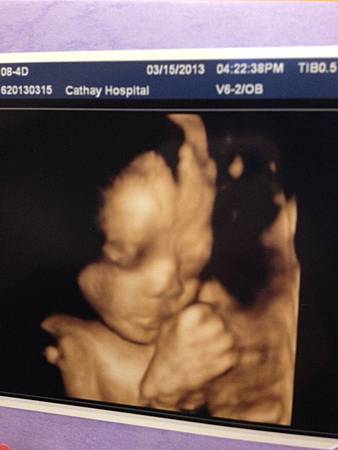

在28週時我們照了有紀念價值的4D超音波~

這次當然也是在國泰做的~ 自費$1500~ 地點與上次做的高層次是一樣的

今天來前我還特別喝了一罐果汁哩~ 因為聽說這樣寶寶比較會動 可以看到比較多的動作與畫面